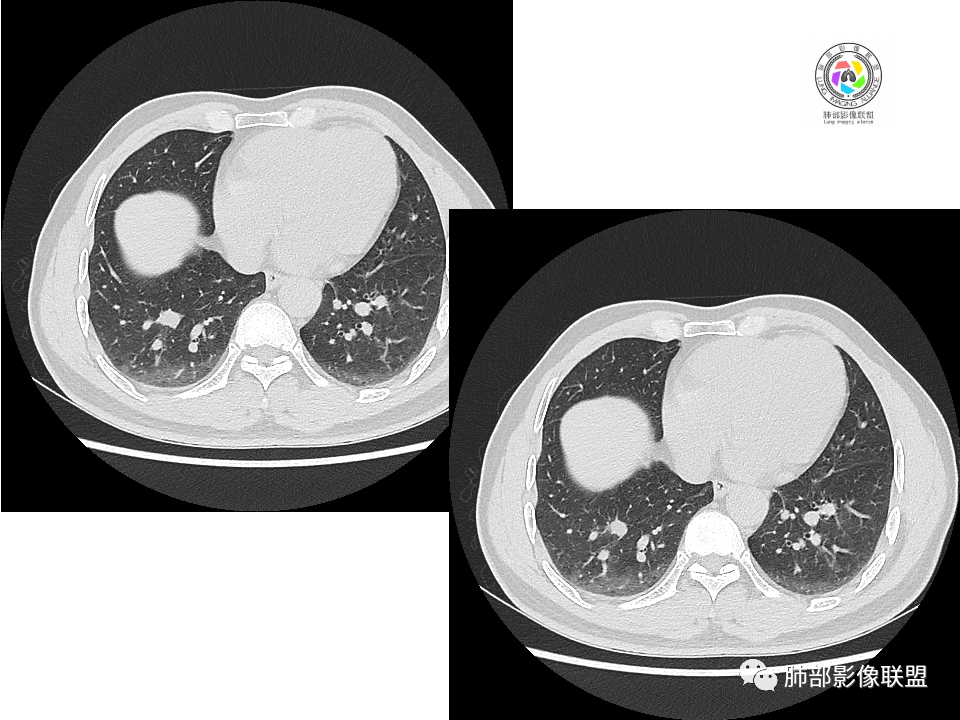

右肺下叶占位,胸膜下,与胸膜关系密切;

密度均匀;糊墙,边缘膨隆为主;

部分血管推移。

支气管如何?

浅分叶

血管也是稍推移,在边缘,病灶密度均匀,边缘稍收缩;均匀强化;

这两个病灶的密度、强化、形态、边缘、与血管的关系类似;还是一元论吧。

右肺中叶病灶

GGO,与支气管关系密切

这个形态、与支气管关系,与前两个不一致,所以考虑独立炎性病变。

2.右肺下叶背段胸膜下块影,边界清楚光整,上下极见磨玻璃晕,未见明显分叶毛刺和棘状突起,未见胸膜凹陷或胸壁侵入。密度均匀,轻度不均匀强化。未见支气管进入。

3.右肺中叶外侧段胸膜下散在小片影,磨玻璃密度为主,边界不清,支气管相关。符合炎性特征!

4.右肺下叶基底段支气管血管束旁小结节影,边界清楚,强化不明显。注意,这结节在“遥远的”基底段。

显然本例焦点在于背段那个边缘光整的块影!